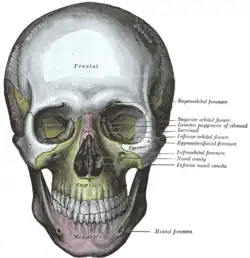

Vista frontal. Maxilar visível ao centro, em amarelo. | |

Nos mamíferos, o maxilar é a estrutura da região frontal do crânio que suporta os dentes superiores e forma uma parte do palato, da cavidade nasal e da órbita ocular[1].

Componentes

Cada metade da maxila fundida pode ser divida em:

- Corpo da maxila;

- Forame infraorbital;

- Seio maxilar e;

- Quatro processos:

- processo zigomático

- processo frontal

- Processo alveolar

- Processo palatino